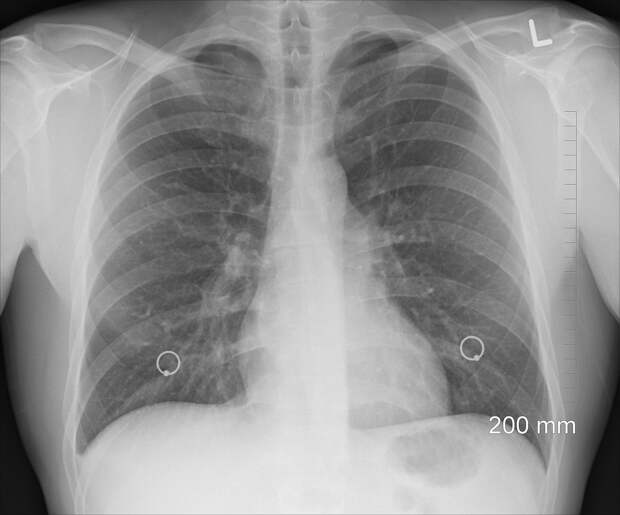

Для постановки диагноза потребуется сбор анамнеза, физикальный осмотр, а также ряд лабораторных исследований, например, посев мокроты на микрофлоры с определением чувствительности к антибиотикам и микроскопией мазка, общий анализ мокроты, общий анализ крови.Игнорировать ХОБЛ не нужно: заболевание будет прогрессировать, ухудшая самочувствие. Болезнь затрагивает не только легкие, но и другие органы, повышая риск развития диабета, остеопороза, рака легких. Кроме того, ХОБЛ влияет на ментальное здоровье, серьезно снижая качеств жизни и провоцируя депрессию.